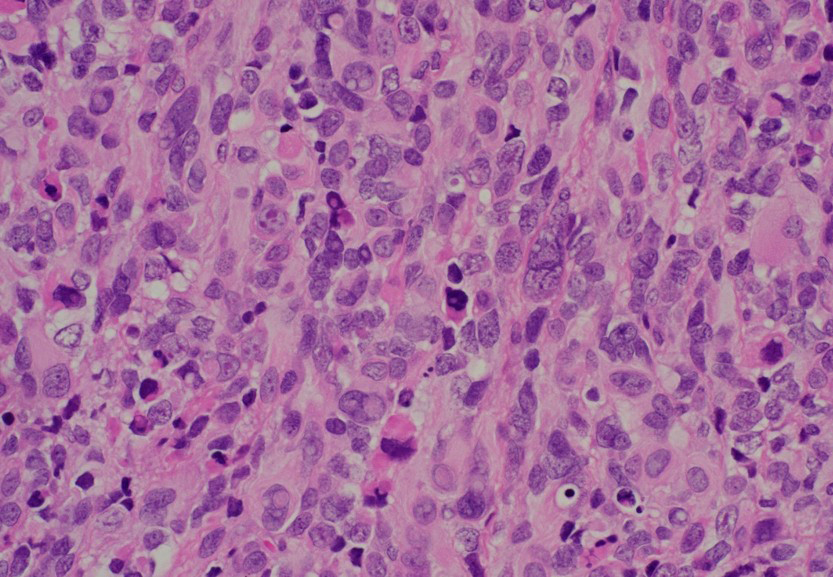

Histologic sections demonstrated a primitive small round blue cell neoplasm arranged in sheets (image 1). The tumor cells were round to polygonal with high nuclear-to-cytoplasmic ratios, vesicular chromatin, prominent nucleoli, and brisk mitotic activity (image 2). Scattered multinucleated tumor cells were identified in addition to cells with eccentrically placed nuclei and abundant eosinophilic cytoplasm (images 3 and 4). Immunohistochemistry showed strong desmin (image 5) and myogenin positivity (image 6) and focal MyoD1 supportive of skeletal muscle differentiation. Stains for cytokeratin, S100, CD45, CD99, and CD34 were negative, excluding epithelial, neural, lymphoid, and vascular neoplasms.